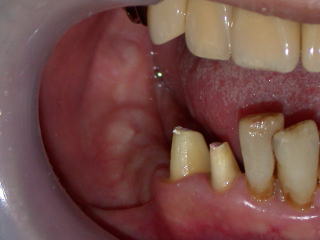

インプラント症例1

43歳男性

初診時平成17年8月

虫歯も歯石もひどく、歯肉は炎症を起こし、口腔内状態は劣悪でした。